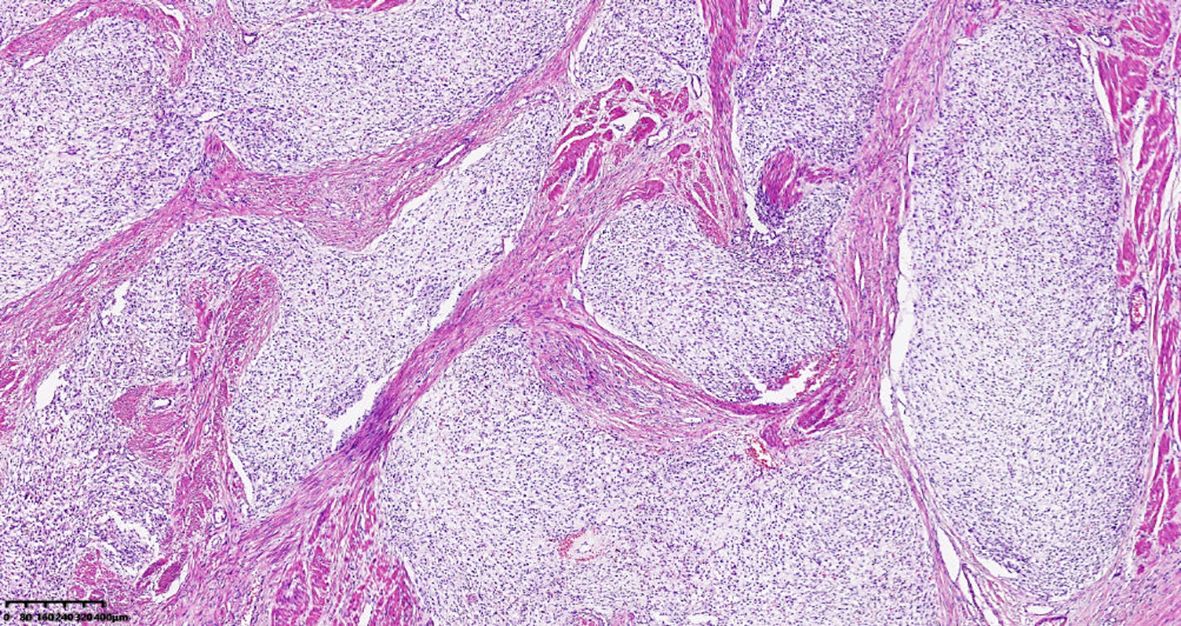

Plexiform fibromyxoma (PF) is a rare mesenchymal tumour that primarily occurs in the stomach, with the antrum and pyloric region being the most common sites. A few cases have also been reported in the duodenum, jejunum, mediastinum, gallbladder, and other locations. Over 100 cases have been reported in the literature, with more than 30 cases reported in our country. A rare case of PF occurring in the cardia and fundus of the stomach is reported in this study. The tumour tissue showed a multinodular, plexiform growth pattern between the muscle bundles of the gastric wall, in which a myxoid matrix and thin-walled vessels were visible. The tumour cells were spindle shaped or short spindle shaped, with a mild change in morphological appearance, and mitotic figures were rare. The tumour cells showed immunohistochemical expression of vimentin and SMA, with focal expression of calponin and CD10. The Ki-67 proliferation index was approximately 5%. The plexiform fibromyxoma was characterized by benign biological behaviour, with surgical excision as the primary therapy. The patient was followed up for about 2 years after surgery without any tumour recurrence or metastasis.